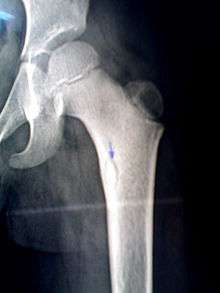

Sequestrum

A sequestrum (plural: sequestra) is a piece of dead bone that has become separated during the process of necrosis from normal or sound bone.

It is a complication (sequela) of osteomyelitis. The pathological process is as follows: